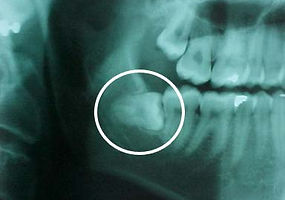

Indicaciones durante su Endodoncia

Antes que nada le agradecemos preferencia por este tratamiento, ya que lo mas importante es conservar sus órganos dentales, ya que aunque la extracción es un camino fácil, definitivamente no es lo mas recomendable. Pues invariablemente existe una pérdida de hueso y además existe una afección en los demás órganos dentales pues puede haber migración de ellos. Ahora debemos de pedirle que siga las indicaciones siguientes para tener éxito en su tratamiento: